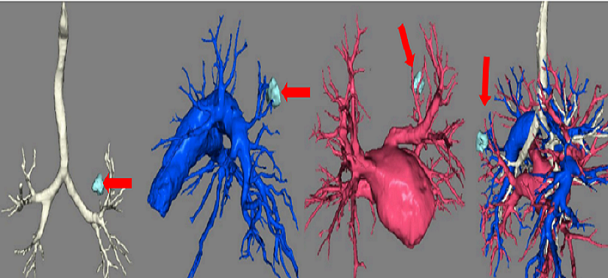

现如今,微创胸腔镜手术已经成为肺GGO、早期肺癌的首选治疗方式。切口选择包括单孔胸腔镜、多孔胸腔镜、剑突下胸腔镜以及机器人手术等等。术式的选择包括肺叶切除,楔形切除,肺段切除,亚肺段切除等等,主要根据患者的病灶大小、位置以及结节多少来决定需要实施的手术方式,但外科医生的技术能力以及经验等因素也决定了手术的切除范围,目前国内外提倡术前CT三维重建、精准定位与个体化施治相结合的治疗原则。

1、三维重建技术有助于亚肺叶切除手术

亚肺叶切除手术包括肺楔形切除、肺段切除和亚肺段切除,亚肺叶切除的体积仅仅占整个肺叶的1/3至1/5,其优点是既可以根治性切除早期肺癌、肺GGO,又可以尽可能多的保留肺功能,目前在世界范围内得到广泛认可与开展,特别适合于年老体弱、肺功能欠佳以及多发肺结节的患者。

CT图像的三维重建技术是对平面轴位图像的补充和扩展,从不同方位及空间,立体显示病变及病变与周围组织的关系,对疾病诊断和定位发挥着重要作用。根据不同病情的需要,三维重建技术又可分为多平面重组(MPR)、曲面重组(CPR)、表面遮盖(SSD)、最大密度投影(MIP)、最小密度投影(MINIP)、仿真内镜(VE)、容积漫游成像(VR)这几种成像技术。通过这种无创的显示技术,可以使得手术更加精准。

图七 三维重建下的肺结节与周围支气管及动静脉的关系